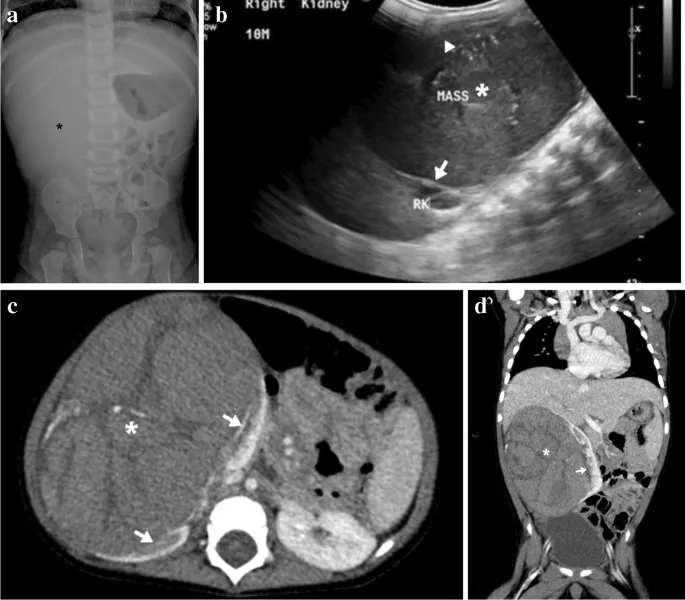

Wilms' Tumor Imaging - Kidney Capers

- Origin: Metanephric blastema; Peak age: 3-4 years.

- Imaging:

- US: Initial, shows intrarenal mass.

ā The 'claw sign' on US/CT, where renal parenchyma is splayed around an intrarenal mass, is characteristic of Wilms' tumor.

- CT: Staging (chest, abdomen, pelvis), contralateral kidney, vascular invasion (renal vein/IVC).

- MRI: Problem-solving (e.g., IVC thrombus extent).

- Features: Well-defined, pseudocapsule; necrosis, hemorrhage common. Typically NO calcification (vs. Neuroblastoma).

- Assess: Contralateral kidney (synchronous tumor/nephroblastomatosis).

- Wilms' tumor: Commonest renal tumor; shows claw sign, respects midline.